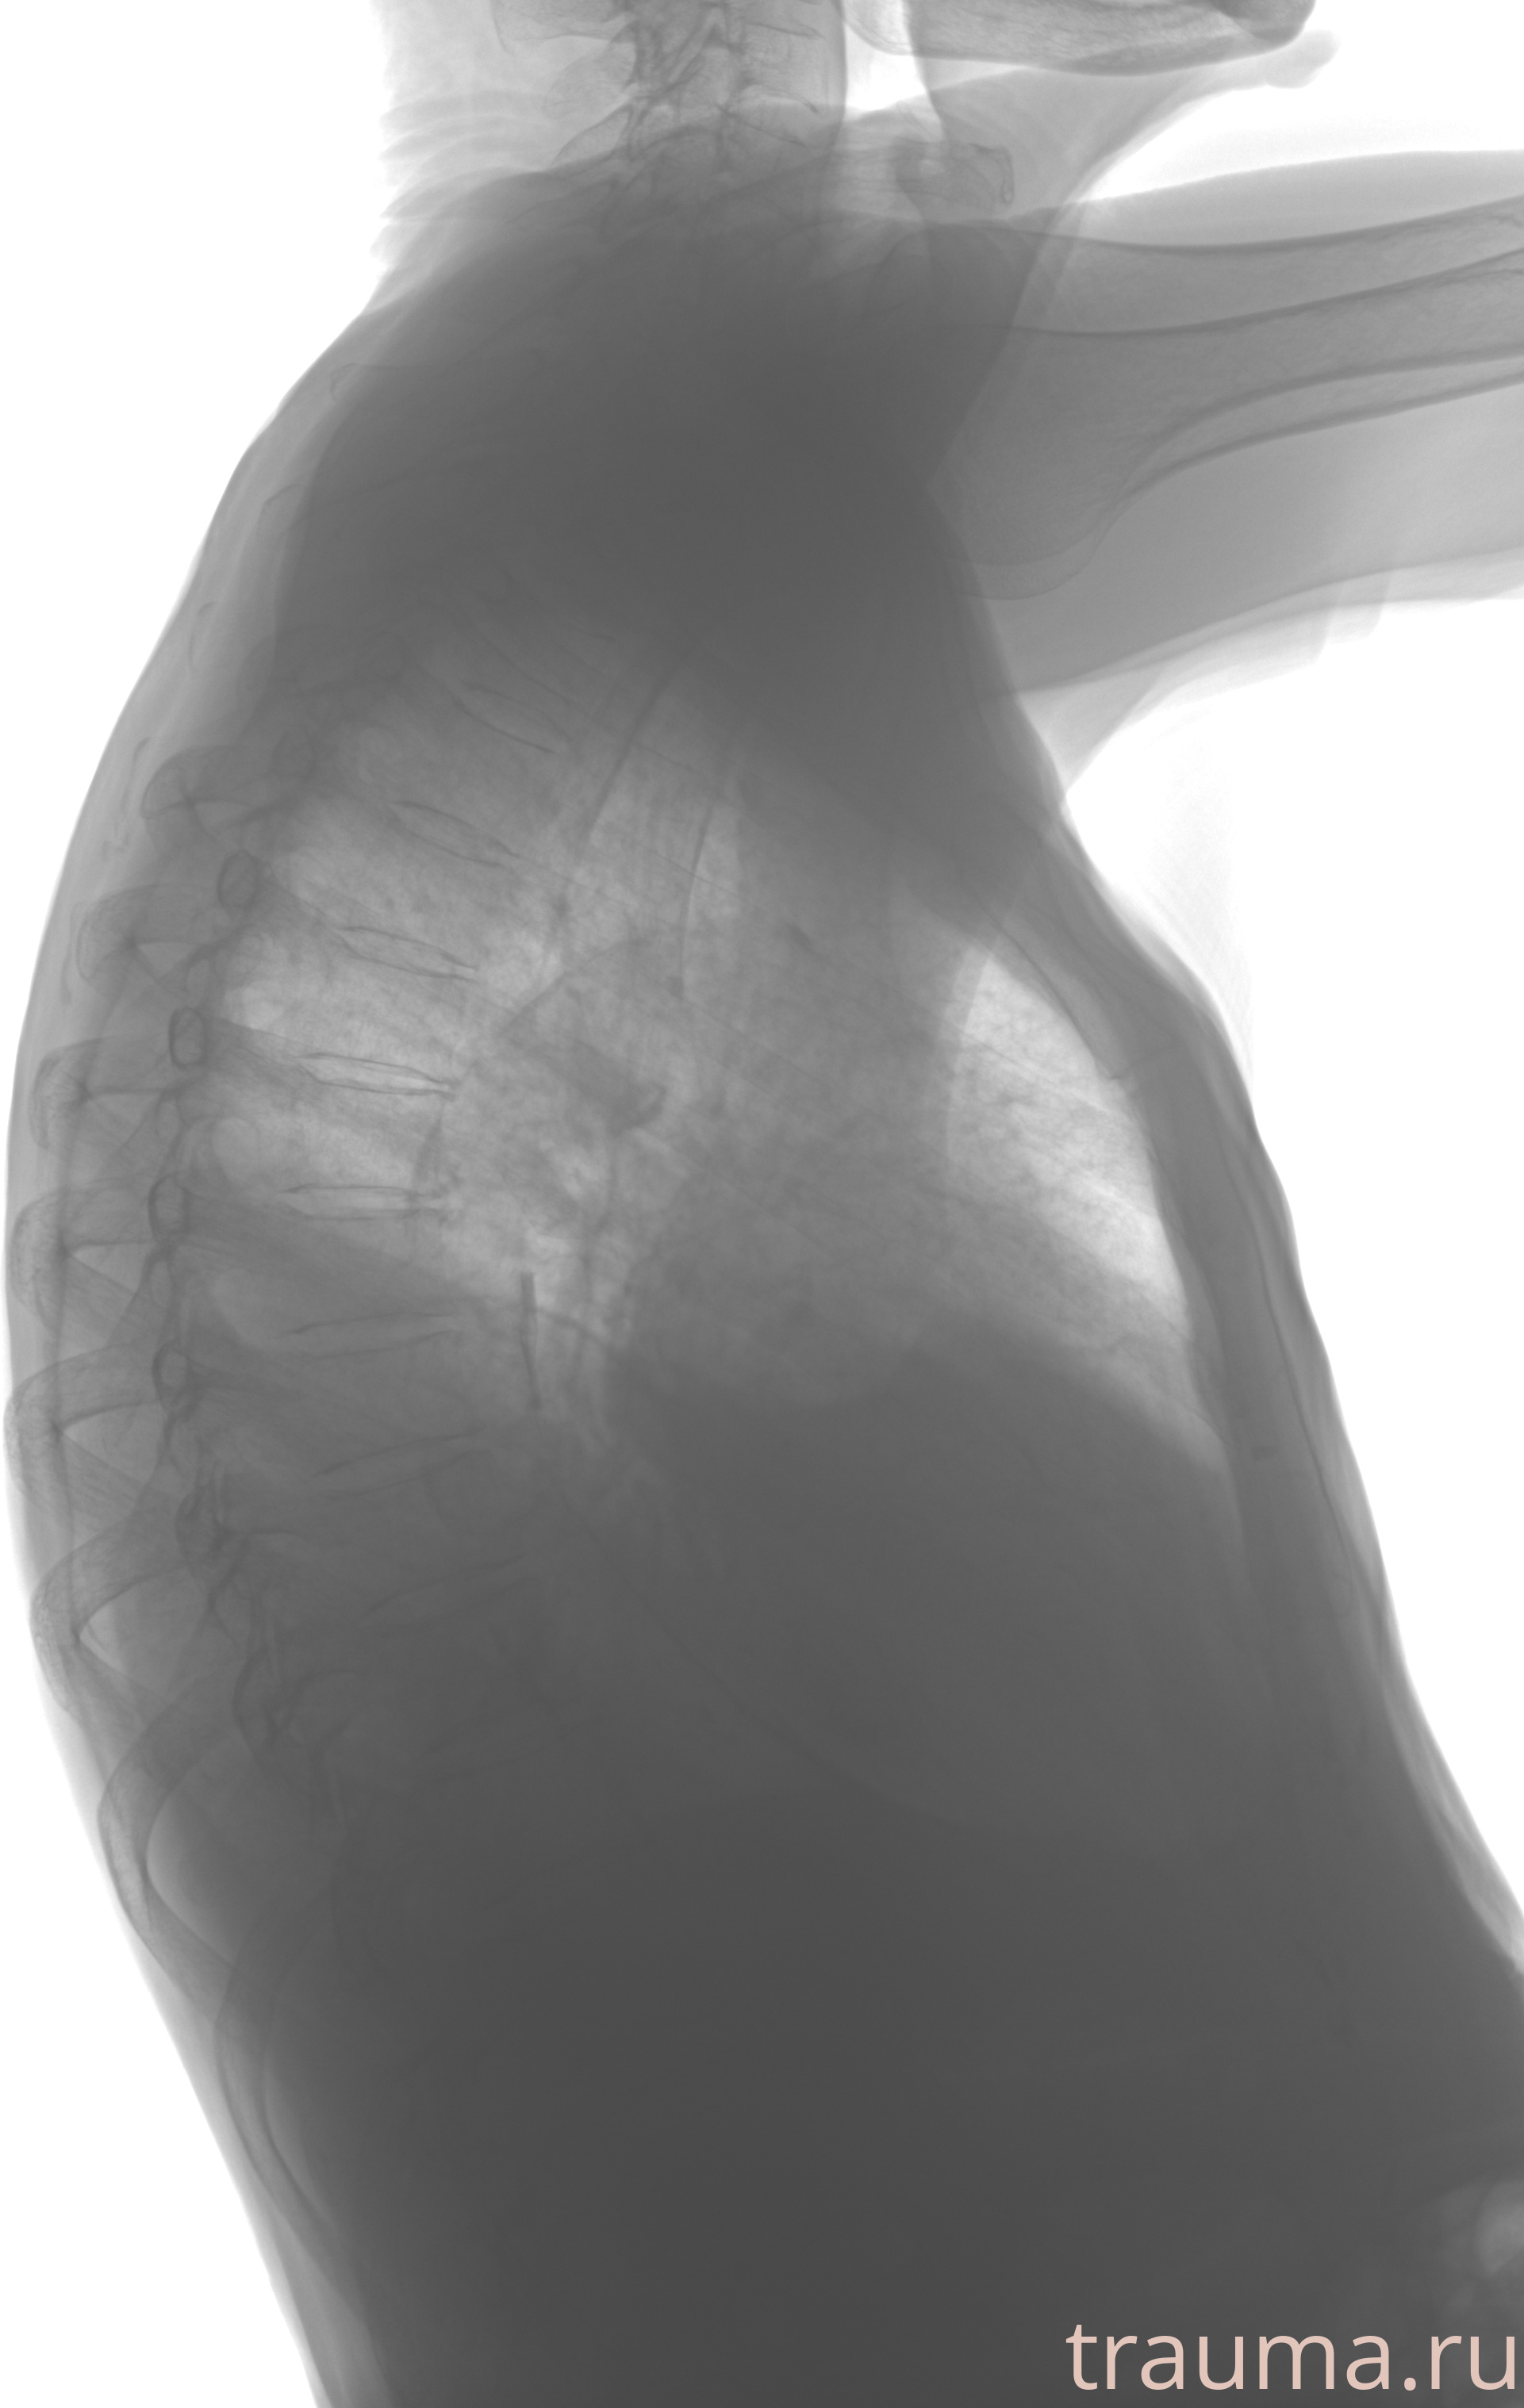

Рентген на дому: по вашему адресу приезжает врач-рентгенолог, травматолог-ортопед с мобильным рентгеновским аппаратом, проводит диагностику травмы или заболевания, делает необходимые рентгенограммы, дает рекомендации по дальнейшему лечению. Получить качественные снимки в домашних условиях возможно благодаря уникальной методике, разработанной МосРентген Центром для института  Склифосовского